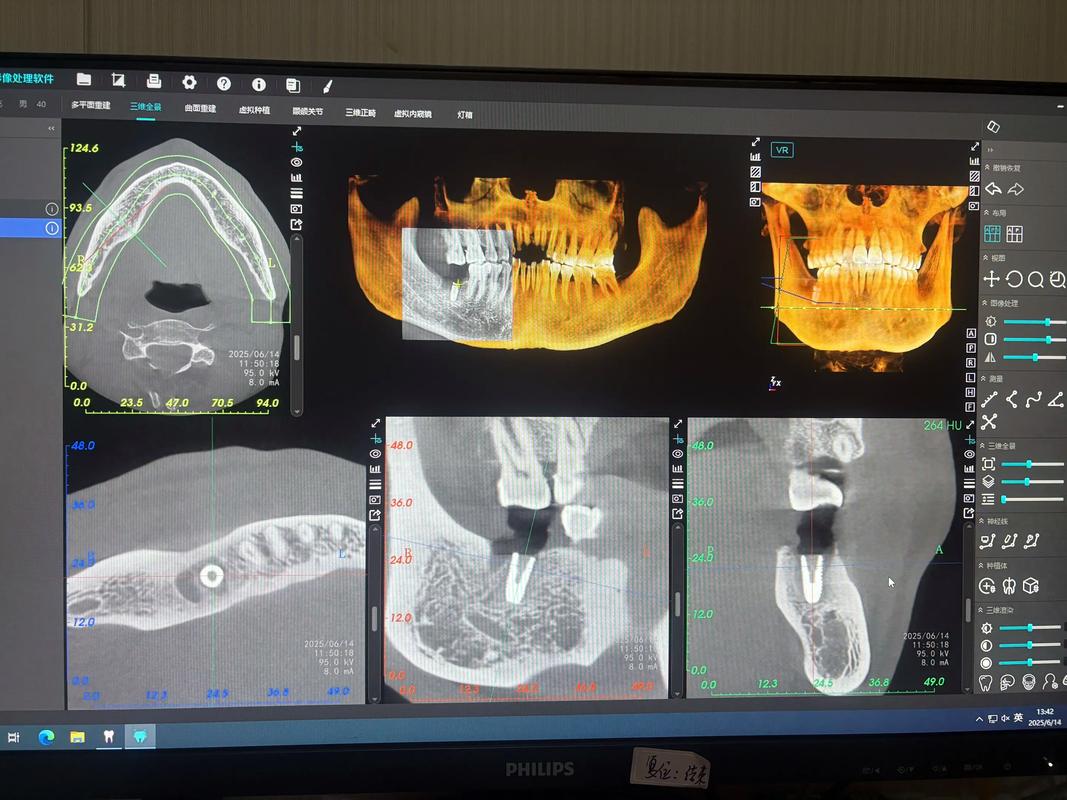

- 医生技术精湛: 需要经验丰富的种植医生进行精确的术前评估(CBCT检查)、术中操作和术后管理。